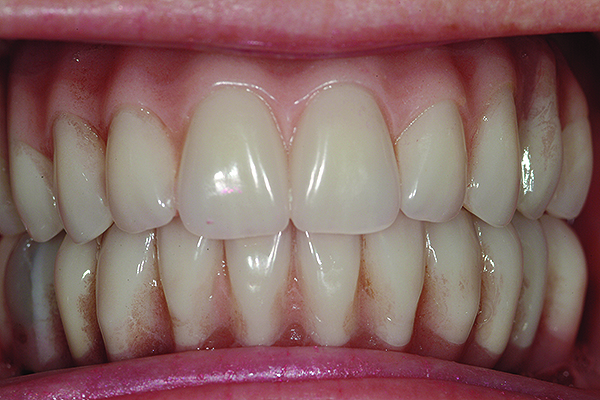

Patient smile shown 3 years post-treatment.

Figure 19